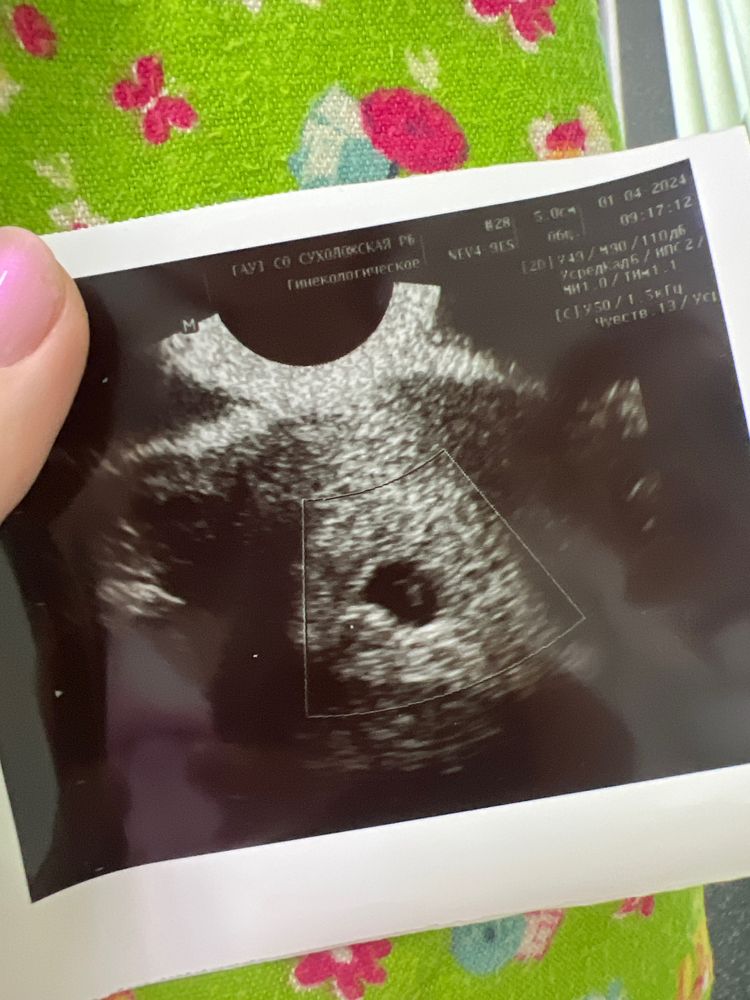

При падающем хгч нельзя уже ничего спасти, организм пытается избавиться от нездоровой беременности,да и по месячным у вас 9 недель уже,а по узи 5,6 и сб нет и хгч уже низкий стал,беременность уже давно замерла и спасать нечего к сожалению,вы наверное хотели услышать что верьте в чудо,но мне кажется что это так себе поддержка,сил и терпения

При 3,7 нет сб … тут к сожалению все понятно😔

Галя, 3,7 это огого какой ктр… сейчас на аппаратах уже при 1.7 видно пульсацию …на фото у эмбрионо прекрасно видно сердечко , значит аппарат нормальный . И не увидеть мерцание невозможно

Галя, так судя по вашим постам у вас в конце февраля хгч уже положительный был,значит ваша овуляция была ещё в середине февраля,уже от овуляции 6 недель прошло,уже совсем другие показатели должны быть, эмбрион уже 15-17 мм на таком сроке,а у вас узи на 5,5 акушерских,это 3,5 от зачатия, беременность ваша замерла давно и хгч уже упал,не тешьте себя ложными надеждами,при нормальной беременности такой ктр в 4 недели от овуляции,а у вас 6 и нет сб даже, беременность уже 2 недели назад замерла